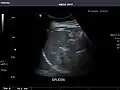

Spleen: Normal in size.

Spleen